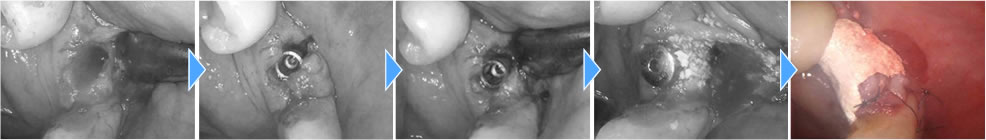

インプラント手術の実施

歯を支えている骨の損傷が大きかったため、骨造成(骨を増やす処置)も追加で行いました。支えがないとせっかく打ったインプラントもしっかり固まらないため、骨造成が効果的なケースがあります。